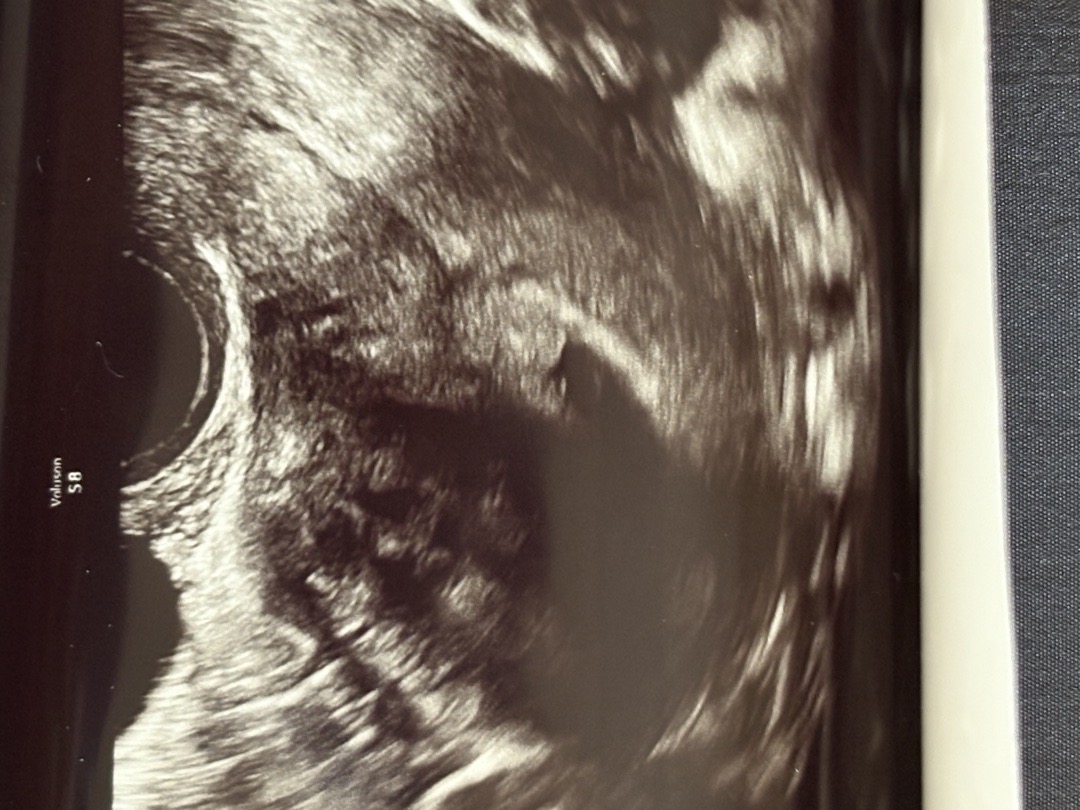

아기집경계가잘안보이는데괜찮은걸까요?

불안핑발동.. 6주차 초음파처음봤는데 다른사람과모양이많이다르네요 초음파보고 더불안해졌어요!ㅜㅜ